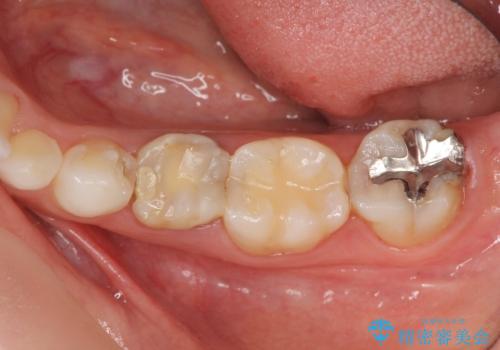

- 大人になっても残存していた乳歯がグラグラし、痛くて噛めない 抜いて欲しいとの希望で来院されました。

歯根が吸収し残すことのできない乳歯を抜去後、隣の歯を削らずに済むインプラント治療で咬合機能の回復を計画します。